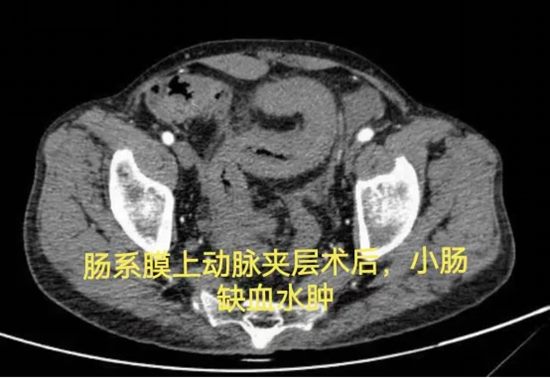

病情简述:53岁男性,肠系膜上动脉夹层术后出现复杂肠瘘,经历三次手术仍无法愈合,入院时白蛋白仅15.0g/L(严重营养不良)。

诊疗破局:面对再次手术的高风险,团队决定“先退一步”,将治疗重点转向营养支持。经过长达3个月的肠内联合静脉营养强化治疗,待患者身体状况改善后,再成功施行“腹腔镜肠粘连松解、瘘口小肠切除+远端回肠及回盲部结肠切除术”,最终成功康复。

技术体现:有时候,充分的术前准备与对手术时机的精准把握,比手术本身更重要。